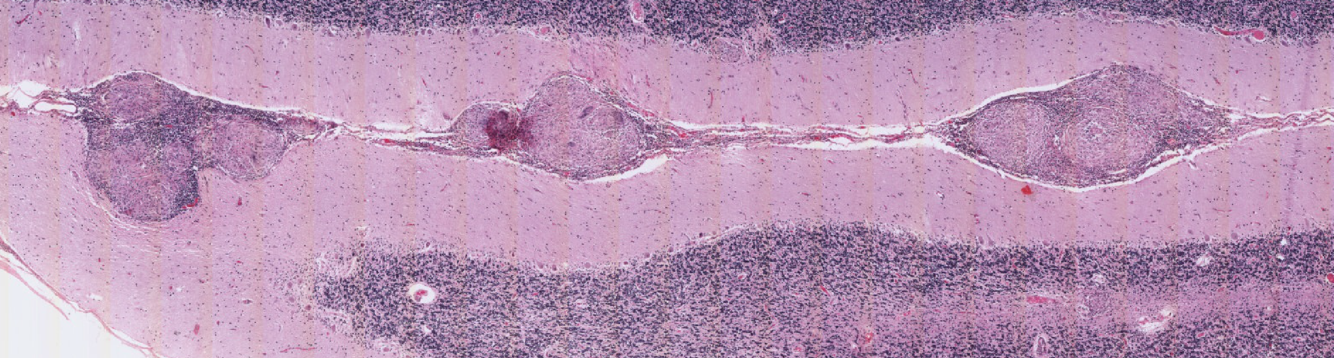

What is this an image of?

Granulomas of the meninges, present in a patient with sarcoidosis